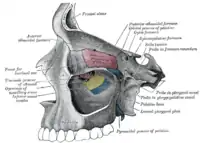

Visão lateral animada. Lacrimal dentro da órbita ocular.

Parede medial da órbita esquerda. Paredes da cavidade nasal.